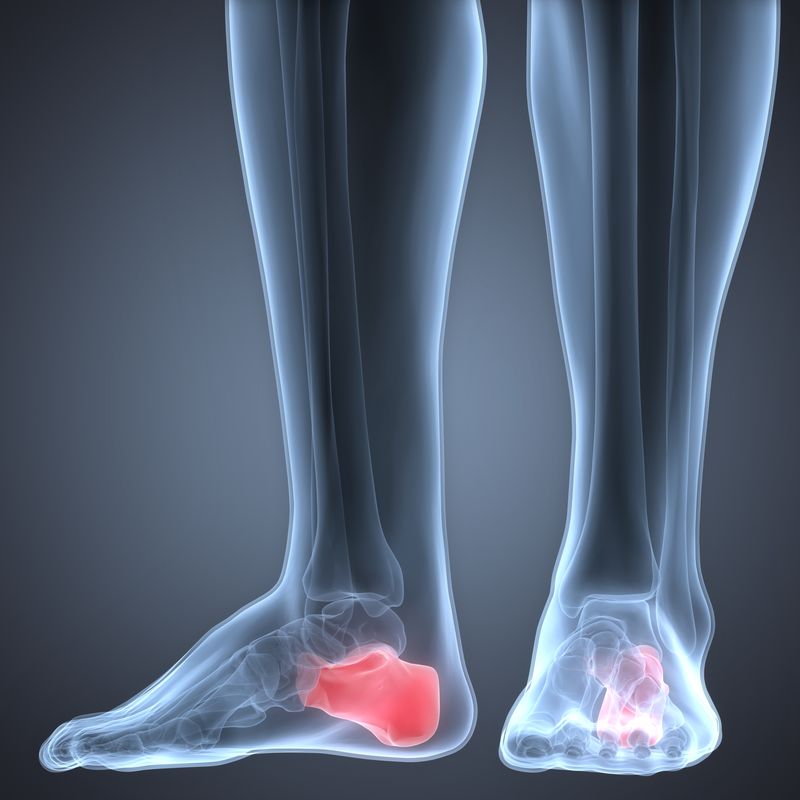

1. Bone Spurs

Osteophytesor bone spurs are small and appear as bumps which protrude from joints affected by osteoarthritis. They are caused when the body tries to mend the breakdown of cartilage. The impact on nearby nerves can create additional problems, including numbness, tingling, and additional pain. This can occur in the spine and lead to difficulty standing and walking, but some people are not even aware of them until they show up on an X-ray.